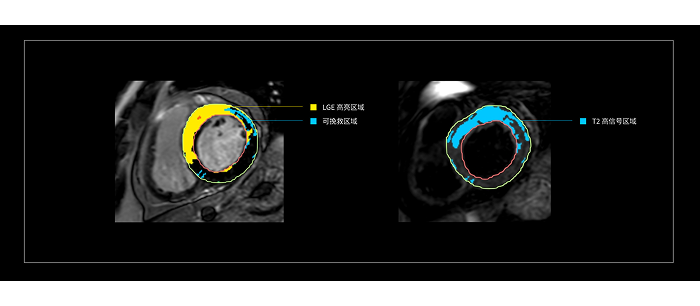

站在医生的角度,联影智能给出的答案是“全自动工作流”。方案内置独家算法,可在数秒内自动对多序列图像(心肌内外膜,水肿、延迟强化区域等)进行自动分割、特征提取、心肌运动追踪。这也意味着,在AI的加持下,医生无需像传统流程一样进行繁复地点击与操作,而是在医生打开软件之后,即可对AI基于影像自动生成的参数及分析结果进行确认或微调。而这是真正可以解放医生精力的事情。